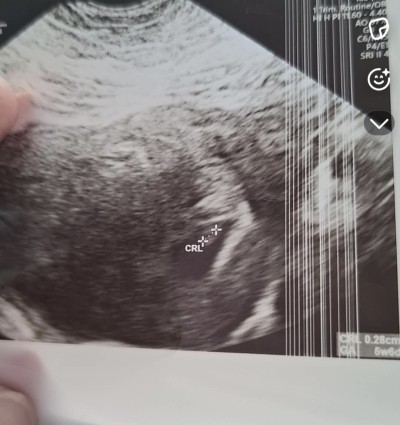

Canim benimki de bir benzerini yaşıyorum suan son adet günüm 21 Eylül kese ekranda zor gözüküyor resmen o kadar küçük ve belli belirsizki anlatamam en son 6+4 de gittim bebek yeni oluşmuş dedi ekrandan kalp atışını görüyorum ama makineye vurdu hiçbir şey duyulmadı bana da 1 2 hafta sonra gel dedi bir sorun var mi dedim bir sorun bence yok dedi kanama filan olursa gel dedi ama şükür bir şeyim yok bende suan 7+6 m 9+1 e denk geliyo gideceğim zaman inşallah o zaman duyarım bende senin gibi merak ve beklenti içindeyim inşallah hayırlı haberler alırız oglumda igne ile olmuştu gunu gününe uyumluydu bu doğal kendiliğinden oldu saglik ocağı hemsiresine sordum ovulasyonun gec olmuştur takılma boyle şeylere dedi benim bebeğim de 3 mm çıkmıştı bak kese ve bebeğin görüntüsünü koydum profilimde en altlara inersen oğlumun kesesi de gözüküyor ama o cok belli ve ikisi de aynı doktor